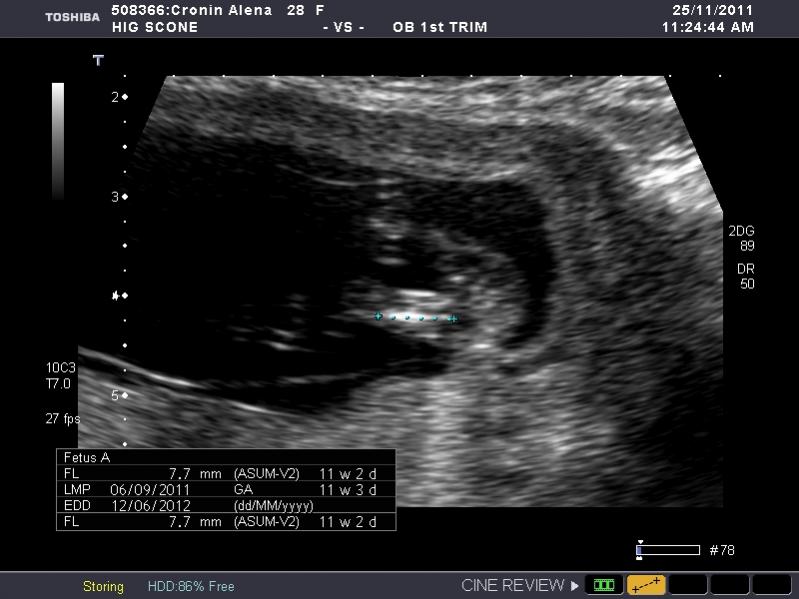

I have heaps of photos and I don't know what I am looking at so if the photo I post isn't showing anything let me know and I will try another. I am nervous as anything because I so so want a girl, but of course would still be happy with a boy. The ultrasound tech wouldn't guess.

So what is your guess.

Attachment 845Attachment 846